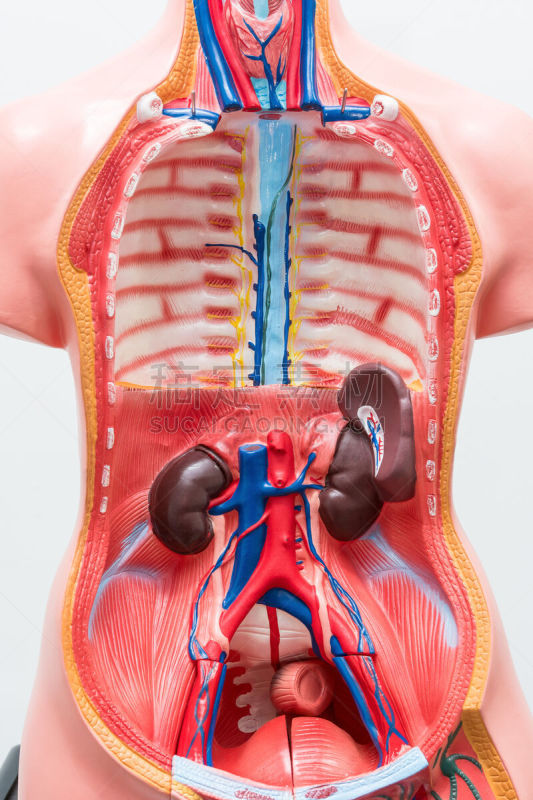

人类隔膜解剖学详情

JPG